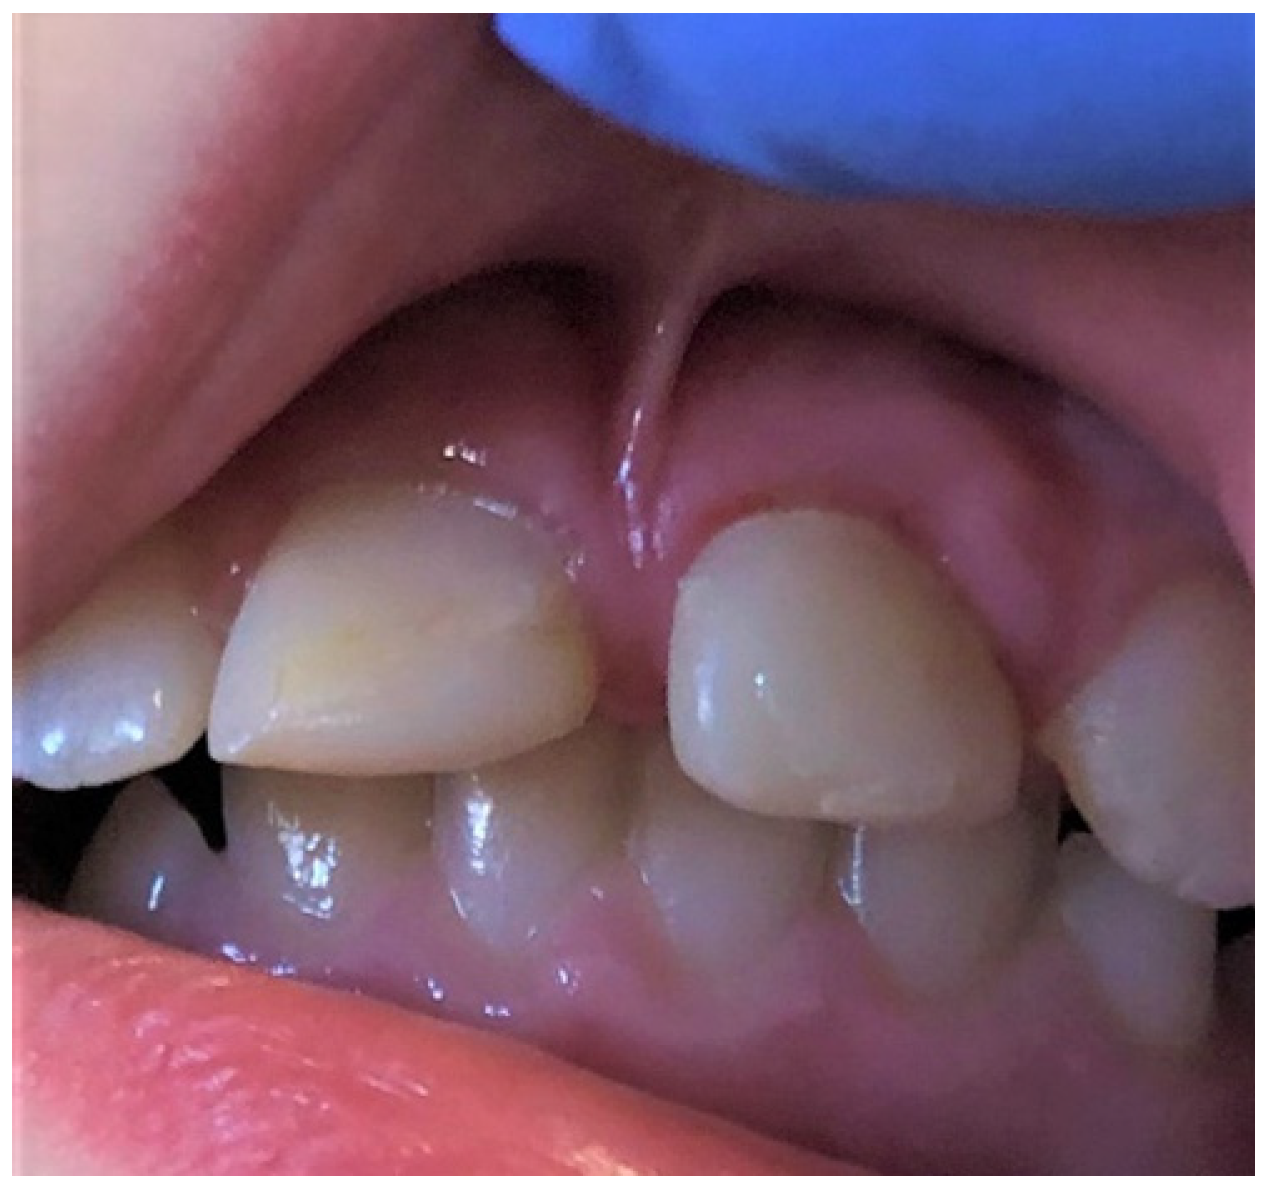

Overgrown or abnormal attachment of the upper lip frenulum may cause diastema, as can be seen in the case from Figure 12, promote the development of caries in the upper central incisors, especially in children, due to hindered tooth brushing, or predispose to periodontal problems [41]. The Placek classification of the upper labial frenulum regards papillary and papilla penetrating attachments as pathological (type III and IV) [42]. In our investigation frenulum attachments, type III or IV were diagnosed in 4.2% of all of the pediatric patients. This figure was lower than those presented by Thilander et al. (5–17 y/o Colombians), Bergese et al. (9–12 y/o Italians), and Kaimenyi (4–16 y/o Nigerian), 17%, 18.1%, and 35%, respectively. This difference may result from the method of selecting patients, as well as their ethnic origin [41,43,44,45]. Additionally, the above-mentioned studies used cross sectional sampling method, where our study was based on patients referring to an oral pathology clinic.

Figure 12.

Overgrown, low, papilla penetrating attachment of the upper lip frenulum (type III acc. Placek) is causing a midline diastema in a school-age girl.

In the present study, overgrown or abnormal attachment of the upper lip frenulum was the 4th most common diagnosed problem in females (6.7%) and the least frequently in males (2.4%), which is in accordance with other investigations [41,43,44,45]. Approximately 7% of the abnormal upper lip frenulum was diagnosed in the age groups 7–13 y/o and in 14–17 y/o, with no cases in the youngest age group (0–6 y/o). For most of the children, 7 y/o is the time to start school, as well as the onset of mixed dentition. During this time, children are confronted with a larger group of peers and people, and the external appearance, including, of course, a smile, begins to play an import role. For some, diastema is a characteristic feature of a smile, and others may consider it a cosmetic defect that may lead to a disturbed self-esteem and start seeking help from a dental professional. This might be the reason for a higher frequency of patients aged 6–17 y/o referring to the clinic with the problem of overgrown or abnormal attachment of the upper lip frenulum.